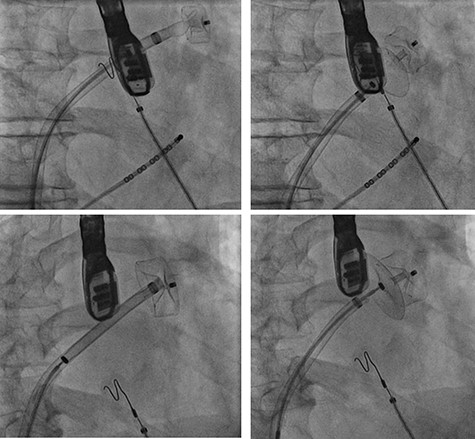

LAA occluder implantation

A treatment review for AF was undertaken, but no further action such as MAZE, pulmonary vein isolation, electrophysiology intervention or rhythm control were considered viable strategies. An LAA occluder implantation (Amplatzer Amulet LAA Occluder, Abbott) was carried out under transoesophageal echocardiography (TEE)-guidance and general anaesthesia (Figs 1 and 2). The left atrium was accessed via the right femoral vein (7F 8.5F catheter). The transseptal puncture with an SL1 catheter was pressure-controlled and TEE-guided posterior–inferior, straight to the optimal position. A 6F pigtail catheter was inserted for LAA angiography in right anterior oblique 30°, cranial 20° and caudal 0°.

Cardiac catheterization: LAA occluder implantation; interventional LAA occluder implantation via the right femoral vein and septal puncture under radioscopy and transoesophageal echocardiography (TEE) control.

The patient’s anatomy showed a large funnel-shaped ostium, with narrow neck and shallow depth and chicken-wing morphology with 90° anterior/frontal angulation. TEE measurements showed a landing zone diameter of ~12–13 mm. A 16 mm occluder was selected. The TorqueVue lock 12F was exchanged via a stiff wire and positioned in the left superior pulmonary vein. No satisfactory position was achieved. For the proximal part, shortly after the ostium with a maximum depth of 12 mm the occluder was too small and exchanged for a 20 mm occluder. This could not be securely positioned; the corpus dislocated in the Timed Up and Go test because of limited contact with the LAA surface. A new transseptal puncture was performed in a more posterior and superior position, the CS catheter removed, and the 7F sheath changed to the SL1. The Amplatzer Amulet 16/20/25 mm LAA occluder implantation remained challenging due to the unusual anatomy with an atypical position of the auricular appendage. Finally the procedure was aborted in favour of a LAA clip.